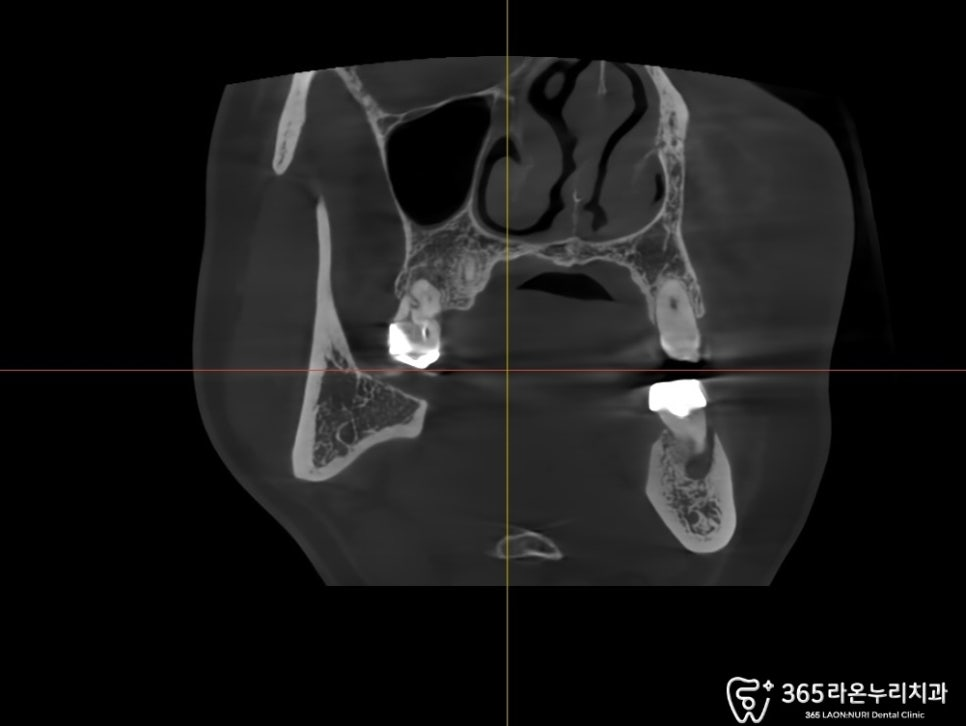

2024.12.20

임플란트 를 심기 전 CT를 통해

확인한 뼈의 형태와 구조를 토대로

식립 위치를 미리 설정했야 됩니다.

국소마취하에 이를 뽑고,

소파술로 병소가 남아있지 않도록

깨끗하게 제거한 다음 해당 부위에

임플란트 를 심는 과정을 가지게 됩니다.